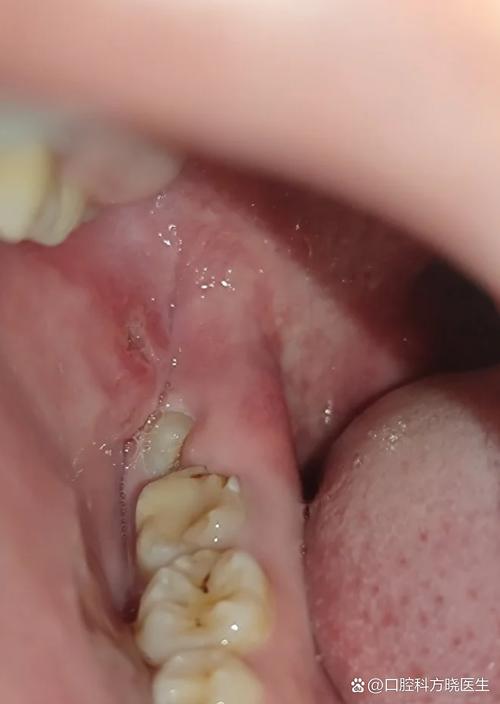

随着智齿继续萌出,如果空间不足,智齿可能会倾斜生长,部分牙龈覆盖在牙冠表面,形成一个盲袋,这个盲袋容易食物残渣和细菌积聚,日常刷牙很难彻底清洁,久而久之,细菌大量繁殖,引发冠周炎,这是长智齿最常见的问题之一,冠周炎的症状会明显加重,牙龈出现剧烈疼痛,疼痛可放射至头部、颈部和肩部,导致患者张口受限,甚至无法正常进食,说话和吞咽也会受到影响,此时牙龈红肿更加明显,表面可能出现脓液,按压时有脓液溢出,同时伴有口腔异味,即使认真刷牙也无法消除,严重时还可能出现发烧、头痛、全身乏力等全身症状,颌下淋巴结也可能肿大并伴有压痛。

不同类型的智齿萌出,症状表现也存在差异,垂直萌出的智齿如果空间足够,可能没有明显症状,仅感觉牙龈轻微不适;而水平阻生智齿更容易压迫邻牙和引发冠周炎,症状通常更严重,部分人可能只有一侧长智齿出现症状,而另一侧无症状,这取决于颌骨空间和智齿萌出方向,女性在怀孕期间由于激素水平变化,牙龈更容易发炎,如果此时长智齿,冠周炎的症状可能会更加明显且难以控制。